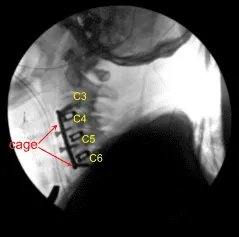

The cage was inserted, again packed with autologous bone graft, Trinity and DBX. After inserting all the three cages, the bony contouring was done using matchstick bur and plate was put of an adequate size. The plate was found to be adequate in AP and lateral views in a satisfactory position.

The plate was fixed using locking variable angle screws in the body of C3, C4, C5, and C6. Final pictures were taken and saved. The wound was thoroughly washed and hemostasis was achieved. The retractors were removed. Closure was done in layers using #2-0 Vicryl and Monocryl. Dressing was applied.